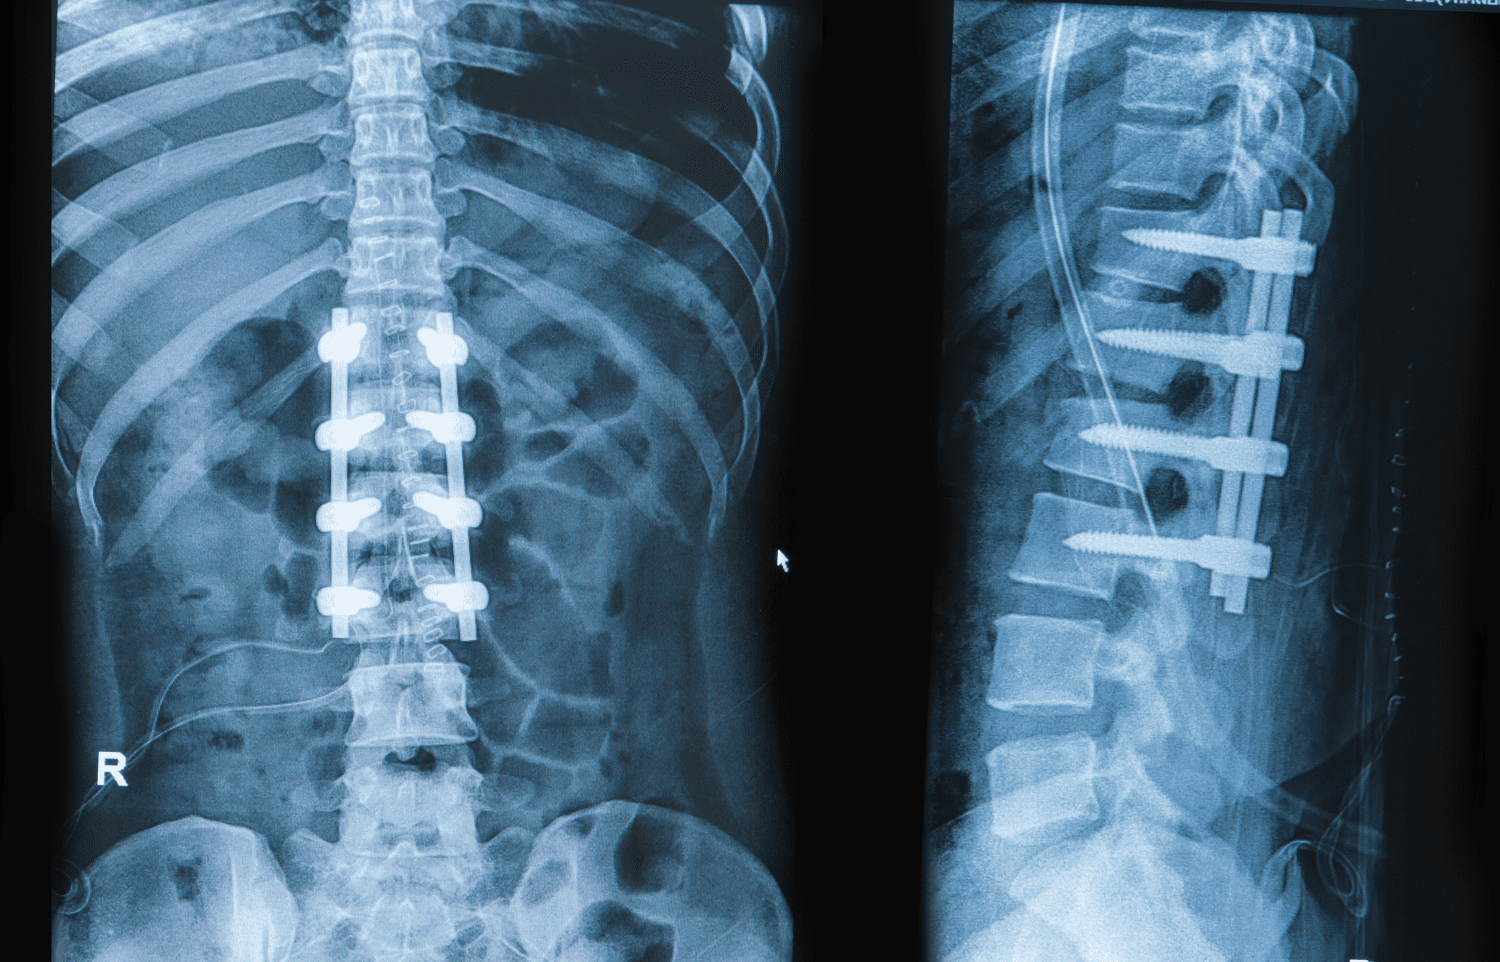

Spine Problem

Dr. Hriday Acharya has trained and worked at prestigious hospitals including Lilavati Hospital, Breach Candy Hospital, Sir H N Reliance Hospital, and B J Wadia Children's Hospital in Mumbai. He has received training from some of the best spine centers in India, Germany, and the USA. Dr. Acharya specializes in Pediatric Spine Deformities, adult spine fracture treatment, and a wide range of spine-related issues for both adults and children.

Speciality Spine Surgeon

Degrees MS Ortho(Gold Medalist) F.ASSI (Mumbai) FISS(USA,Germany)

Experience Of: 22+ Years

Spine Fractures